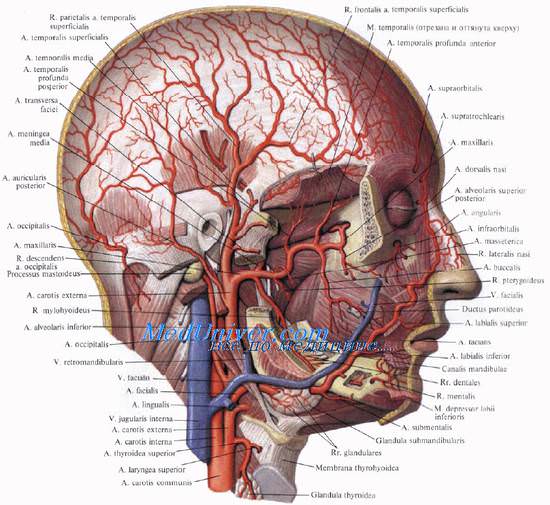

Кровоснабжение, иннервация полости носа и лимфоотток Главной артерией, питающей стенки носовой полости, является a. sphenopalatine (из a. maxillaris). В передней части полости разветвляются аа. ethmoidales anterior et posterior (от a. ophthalmica). Вены наружного носа вливаются в v. facialis и v. ophthalmica.

Кровоснабжение наружного носа осуществляется a. dorsalis nasi (конечная ветвь a. ophthalmica) и ветвями лицевой артерии. Вены связаны с лицевыми венами и с истоками глазных вен.

Кровоснабжение околоносовых пазух происходит из ветвей внутренней и наружной сонных артерий, главным образом через глазную и верхнечелюстные артерии. Вены гайморовой пазухи анастомозируют с венами лица и крыловидного сплетения, а вены лобной пазухи — с венами твердой мозговой оболочки, с продольным синусом и пещеристым синусом. По этим путям иногда проникает инфекция в глазницу или полость черепа.

Иннервация околоносовых пазух осуществляется от I и II ветвей тройничного нерва, а также от крыловидно-небного узла.